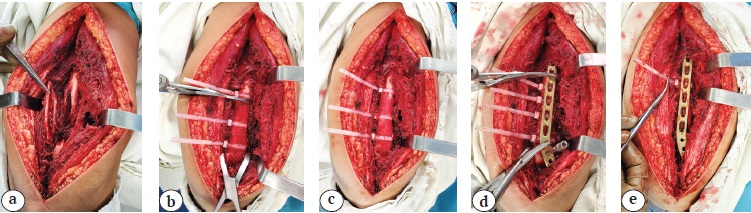

Хомуты-стяжки перед операцией подвергают стерилизационной обработке в стандартных режимах, предназначенных для подготовки полимерных изделий. Методика применения хомутов-стяжек во время остеосинтеза отличается простотой. После выделения отломков осуществляют их репозицию и удержание с помощью зажимов и костодержателей по обычной методике. Именно на этом этапе операции и возникает потребность в применении разработанного нами способа, так как наложенные на кость костодержатели препятствуют укладке пластины на кость (рис. 2 a). Для этого на свободные от костодержателей участки кости в области стыковки отломков накладывают 3–4 пластиковых хомута-стяжки (рис. 2 b). В тех местах, где к отломку прикрепляются неповрежденная надкостница и мышцы, инструментом формируют узкие поперечные каналы в мягких тканях для обхватывания кости хомутом. Затем свободный конец хомута проводят через его замок и максимально затягивают. После затягивания всех хомутов костодержатели снимают (рис. 2 c). Наложенные хомуты надежно удерживают костные фрагменты от каких-либо смещений даже при ротации сегмента. Затем поверх кости с затянутыми хомутами-стяжками укладывают накостный фиксатор (рис. 2 d). При необходимости ему придают неподвижность с помощью костодержателя или дополнительных хомутов. После этого начинают фиксировать пластину к кости винтами. Важно исключить сильное зажатие хомута под пластиной. Если пластину укладывают на кость без сильного прижатия, то стяжки будут удаляться из-под пластины без труда на любом этапе остеосинтеза. Если же пластину притягивают к кости костодержателями или кортикальными винтами, то лучше удалять стяжки до этапа вкручивания ближайших к месту перелома винтов, чтобы избежать их плотного зажатия под пластиной. Для дополнительного ослабления придавливания стяжки рядом с хомутом в щель под пластину можно ввести малый элеватор или крючок малого ретрактора Хомана и отдавить фиксатор от кости. Стяжки удаляют, разрезая их скальпелем или перекусывая кусачками (рис. 2 e). После этого пластину закрепляют к кости оставшимися винтами.

Рис. 2. Этапы использования хомутов-стяжек для удержания костных отломков:

a — положение отломков до начала репозиции; b — после наложения костодержателей и хомутов-стяжек; c — после снятия костодержателей; d — после наложения пластины; e — удаление хомутов-стяжек

Fig. 2. Stages of using ty-raps to hold bone fragments:

a — the position of the fragments before the start of the reposition; b — after applying the bone clamps and ty-raps;

c — after removing the bone clamps; d — after applying the plate; e — removing the ty-raps